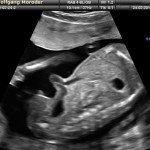

L’ecografia è una tecnica che consente di vedere gli organi del nostro corpo con l’utilizzo di onde sonore ad alta frequenza (ultrasuoni, non udibili dall’orecchio umano) che attraversano i tessuti. La sonda ecografica invia impulsi di onde sonore nel corpo. Quando le onde sonore arrivano al feto mandano degli echi: tali echi (o onde di ritorno) sono trasformati in immagini sul monitor dell’ecografo. Con l’ecografia è quindi possibile osservare in modo dettagliato il feto.

Le ragioni più comuni per cui si esegue una ecografia in gravidanza sono: determinare il numero degli embrioni o dei feti, visualizzare l’attività cardiaca fetale, determinare l’epoca di gravidanza, valutare l’anatomia e la crescita fetale, determinare la posizione del feto e della placenta

Nei primi mesi di gravidanza, con la misura della lunghezza del feto, è possibile valutare se lo sviluppo corrisponde all’epoca di gravidanza valutata in base alla data dell’ultima mestruazione, il numero dei feti e la presenza dell’attività cardiaca.

Dal secondo trimestre si misurano altre parti fetali, ed i valori di tali misure vengono confrontati con quelli delle curve di riferimento. Si può così valutare la normalità o meno della crescita fetale. Inoltre periodo si visualizzano la sede di inserzione placentare e la quantità di liquido amniotico.